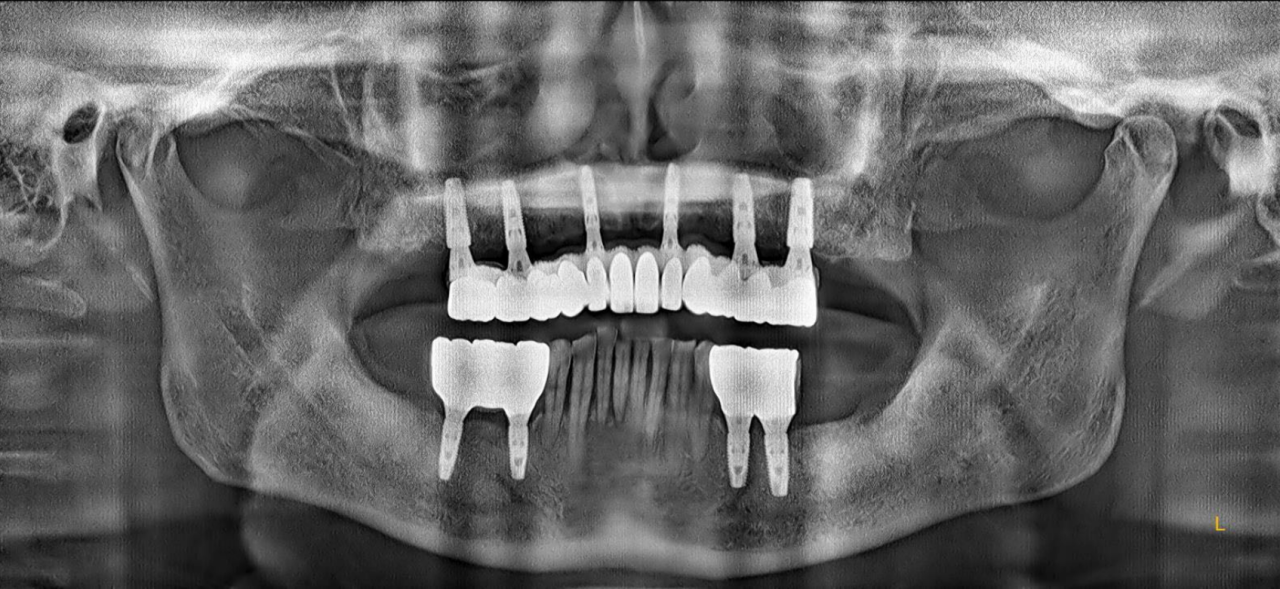

X线检查:上颌余留牙牙槽骨吸收至根尖1/3,预留骨量尚可,骨密度II-III类。

CT检查:后牙余留骨量高度10-12mm,前牙骨高度12-14mm,宽度均大于6mm。

上颌植入6颗中科安齿种植体